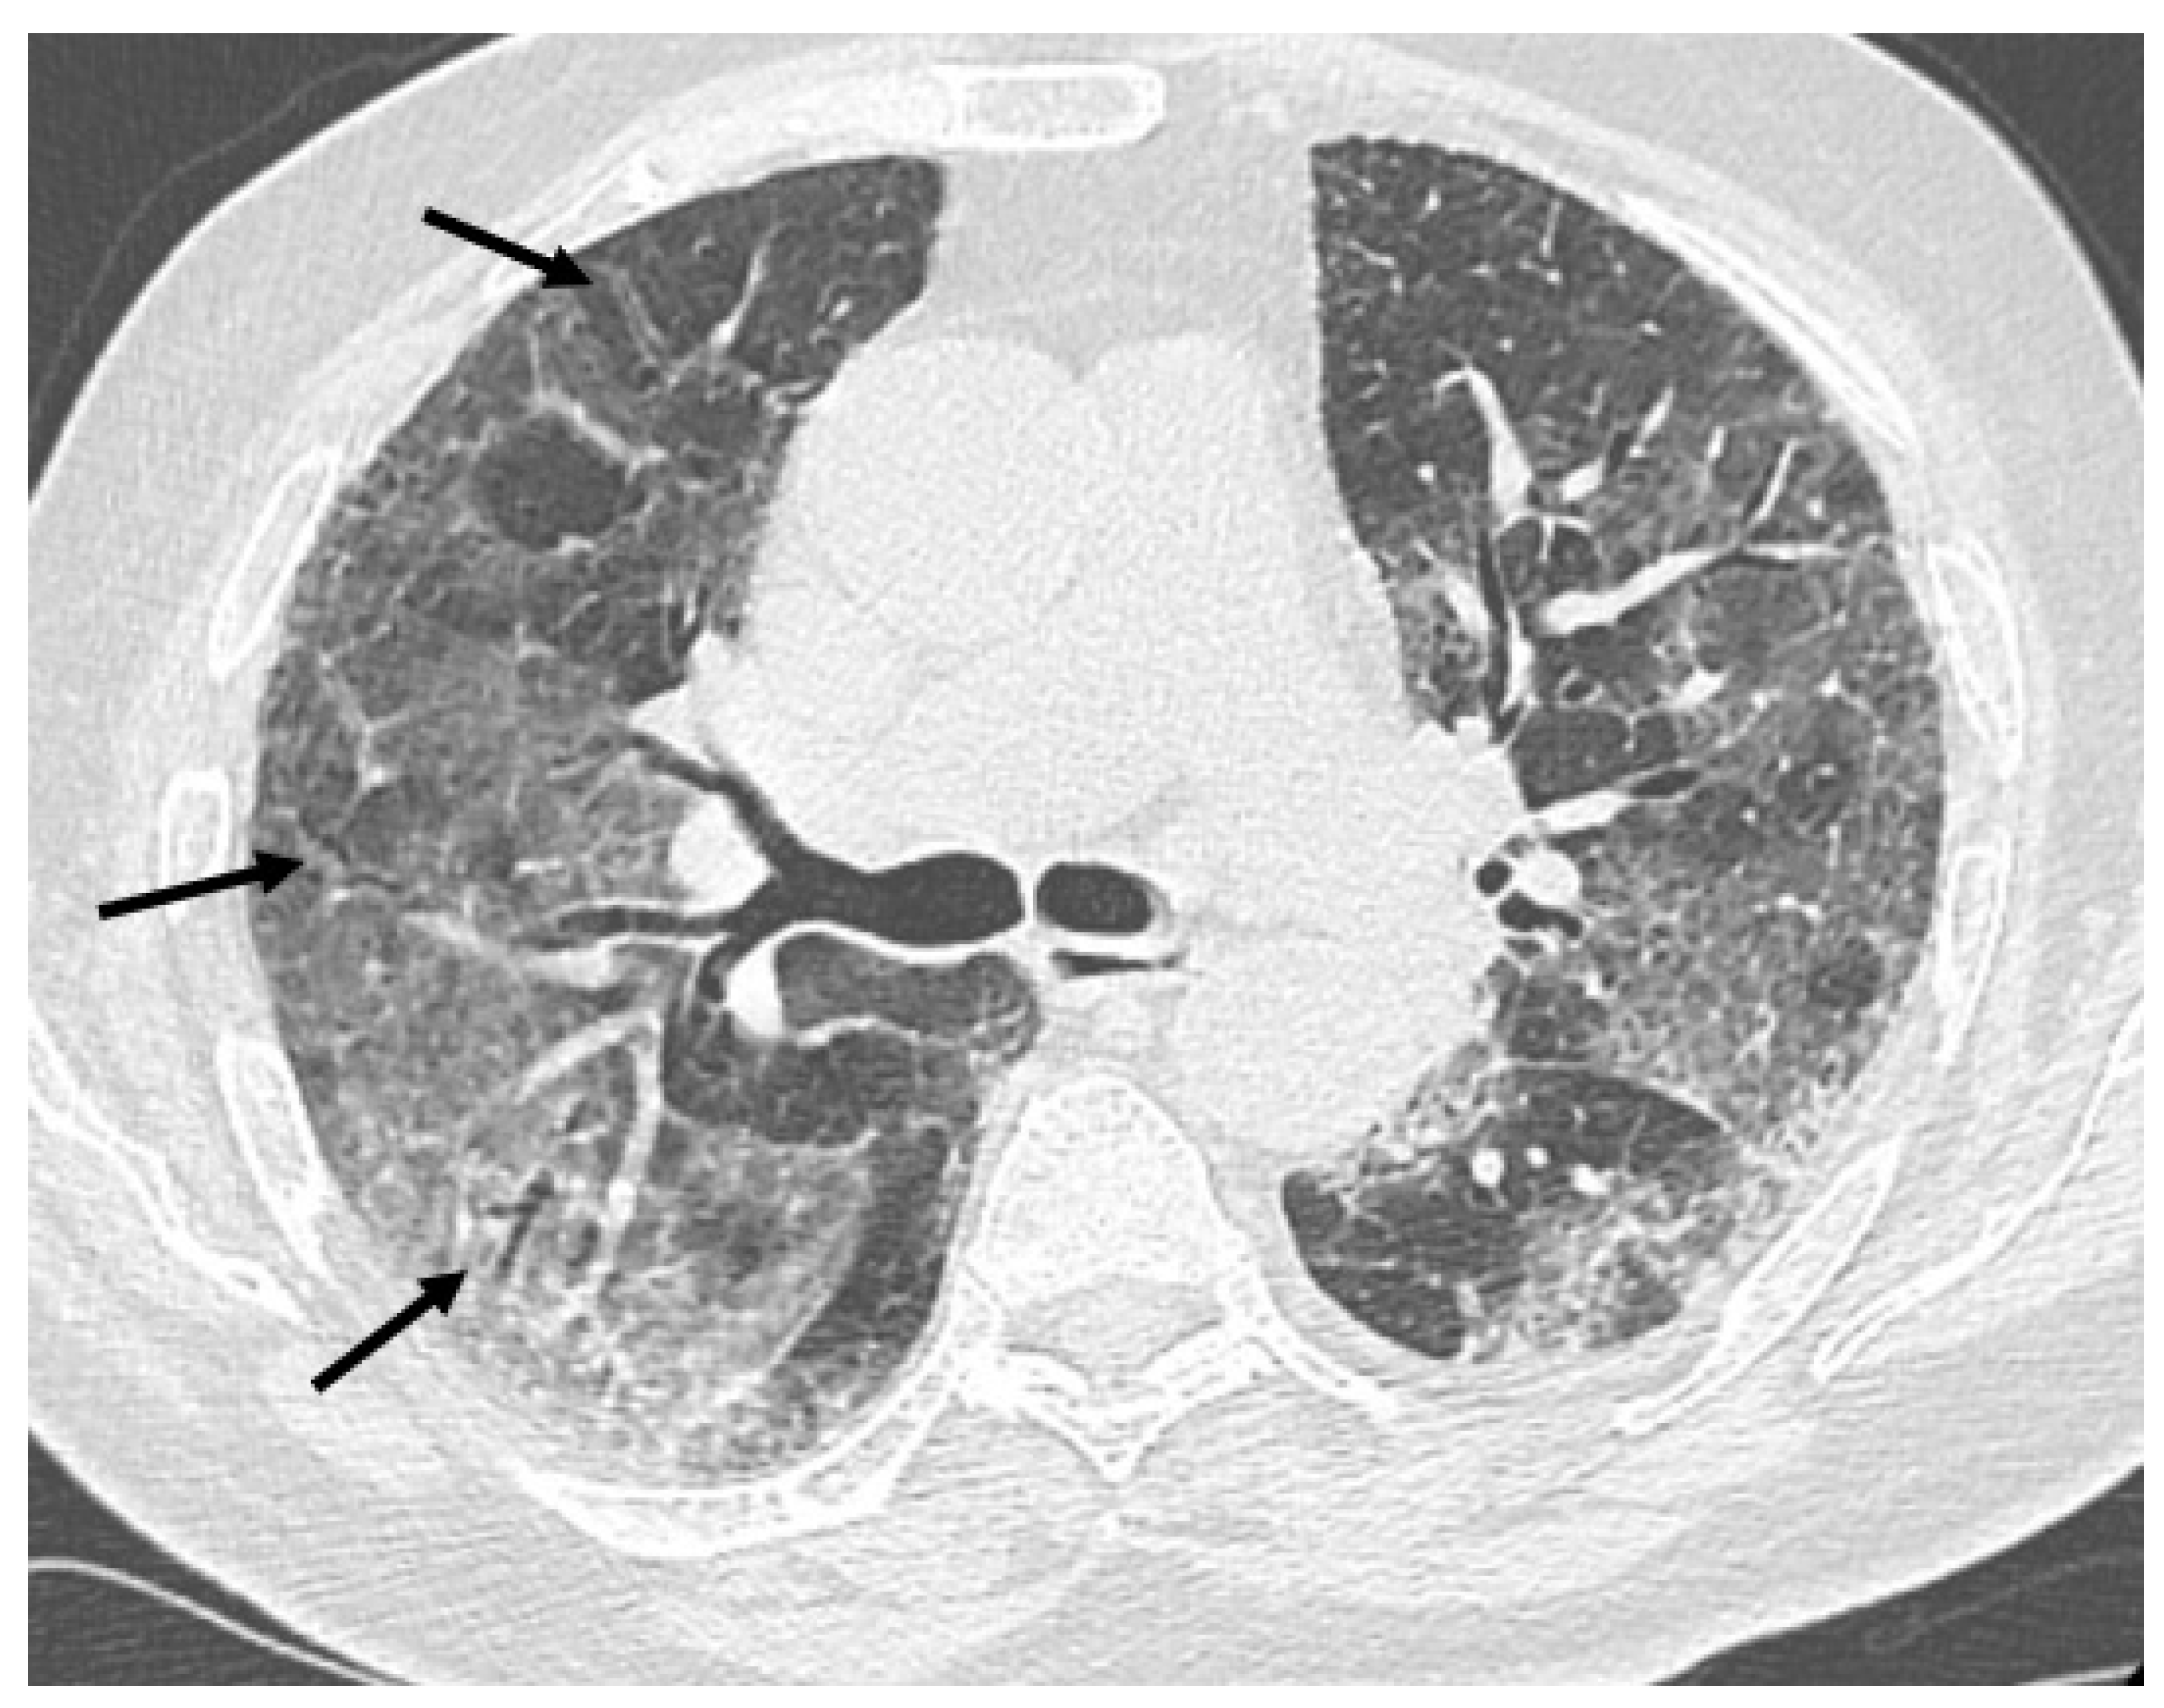

HRCT of the chest showed diffuse bilateral ground glass opacities (GGO) in all patients (Figure 1). Reticulation (Figure 2), traction bronchiectasis/bronchiolectasis (Figure 3), crazy paving and distortion (Figure 4) were observed in 29 patients (64%) at baseline. The total severity score was significantly higher at baseline in patients who eventually developed severe versus non-severe ARDS and pneumomediastinum/pneumothorax (16 versus 14; 95% CI 0.42 to 3.88; p = 0.01), as reported in Table 1. No other significant difference was observed at baseline.

Figure 2.

Reticular pattern (arrows) at baseline and massive pneumomediastinum after non-invasive ventilation in a 60-year-old man.